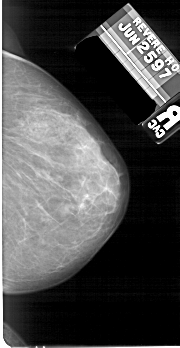

A_1673_1.LEFT_MLO

LEFT_MLO LINES 5491 PIXELS_PER_LINE 2806 BITS_PER_PIXEL 12 RESOLUTION 43.5 OVERLAY